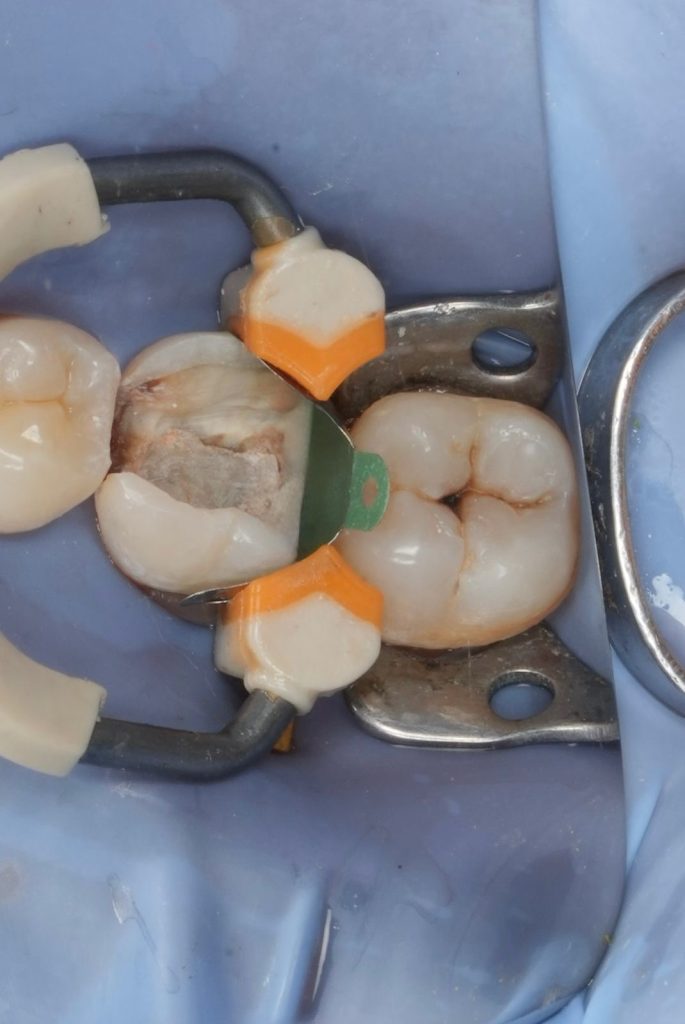

Deep Margin Elevation (DME)

- Distal subgingival margin elevated using flowable resin (GC EverX Flow / Equivalent).

- Garrison sectional matrix used to ensure tight proximal contact and emergence profile.

- Adhesive protocol respected to optimise bond.

Definitive Restoration

- Core build-up completed using dual-cure composite core material.